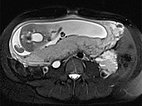

Coronal (top) and axial (bottom) T2-weighted sequences without contrast at 21 weeks' gestation.

Marked increase in size of the VM during pregnancy, which is visualized ventrally of the left psoas muscle as a signal-intense lesion, without displacement or compression of the placenta.

Coronal T2 sequences depicting progression of the VM ventrally sitting on the left psoas muscle at 21 weeks’ gestation. During pregnancy, the patient also develops grade 3 right-sided hydronephrosis.

In the axial T2-HASTE sequence at 21 weeks' gestation, the VM is adjacent to the placenta without displacement of the uterus or fetus.